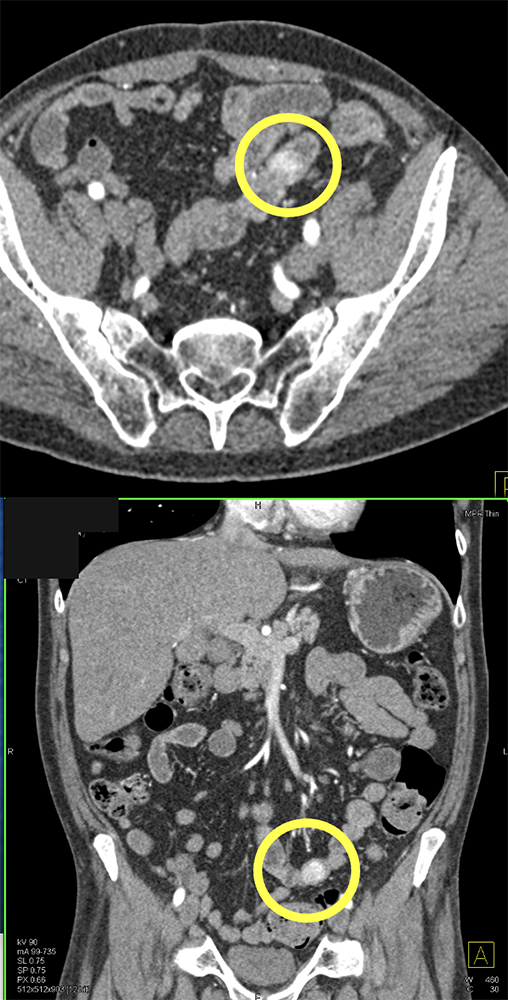

GI Bleed in Patient with Crohn’s and had Atrial Fib on Anticoagulants ![]() |

![]() |